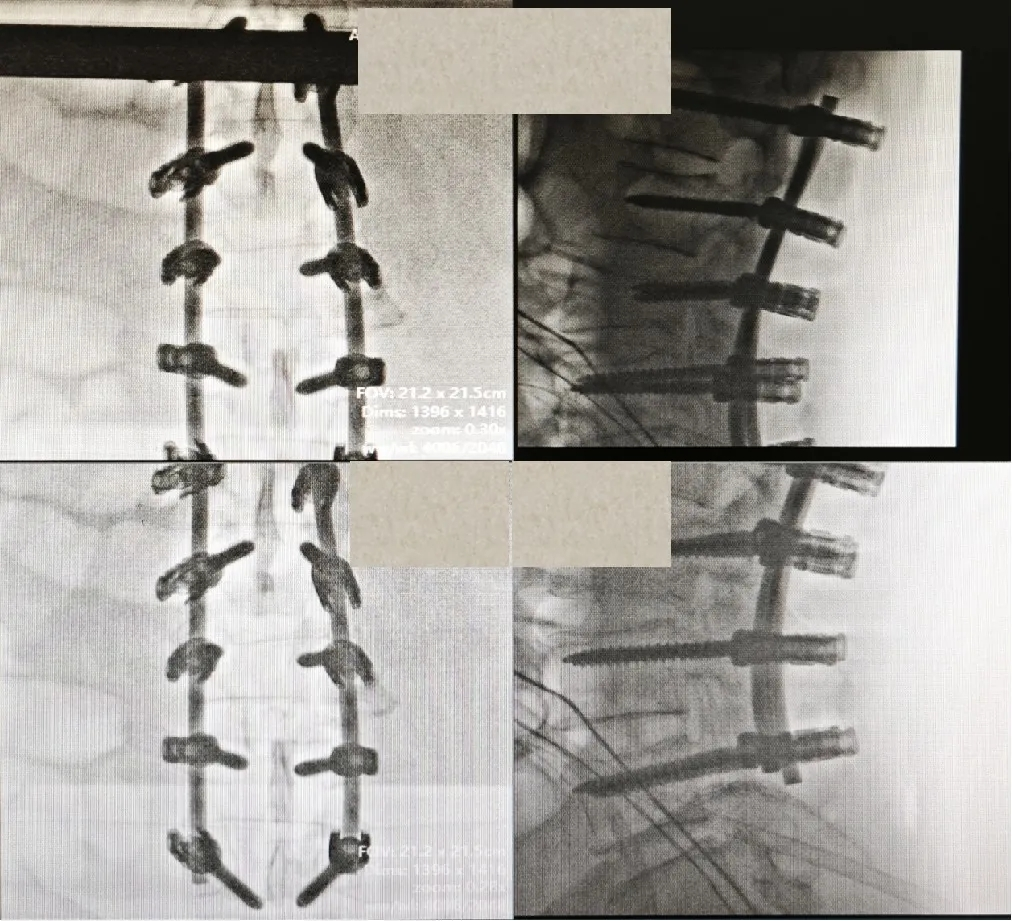

从凌晨四点忙碌到上午十点,跨越了值班的交界,团队无人言退。在完善所有必要准备后,患者被送入手术室,行 “腰椎后路减压切开复位植骨融合内固定术(L1-L5)” 。手术复杂,需在保护受损神经的同时,精细复位爆裂的椎体、牢固固定。最终,周日下午三点多,手术团队成功清除了椎管内的骨折碎片,脊柱序列复位良好,为患者后续神经功能的恢复打下了坚实基础。

术中团队奋战,为患者保驾护航

术后复位效果满意,爆裂的椎体复位良好,椎管内压迫解除